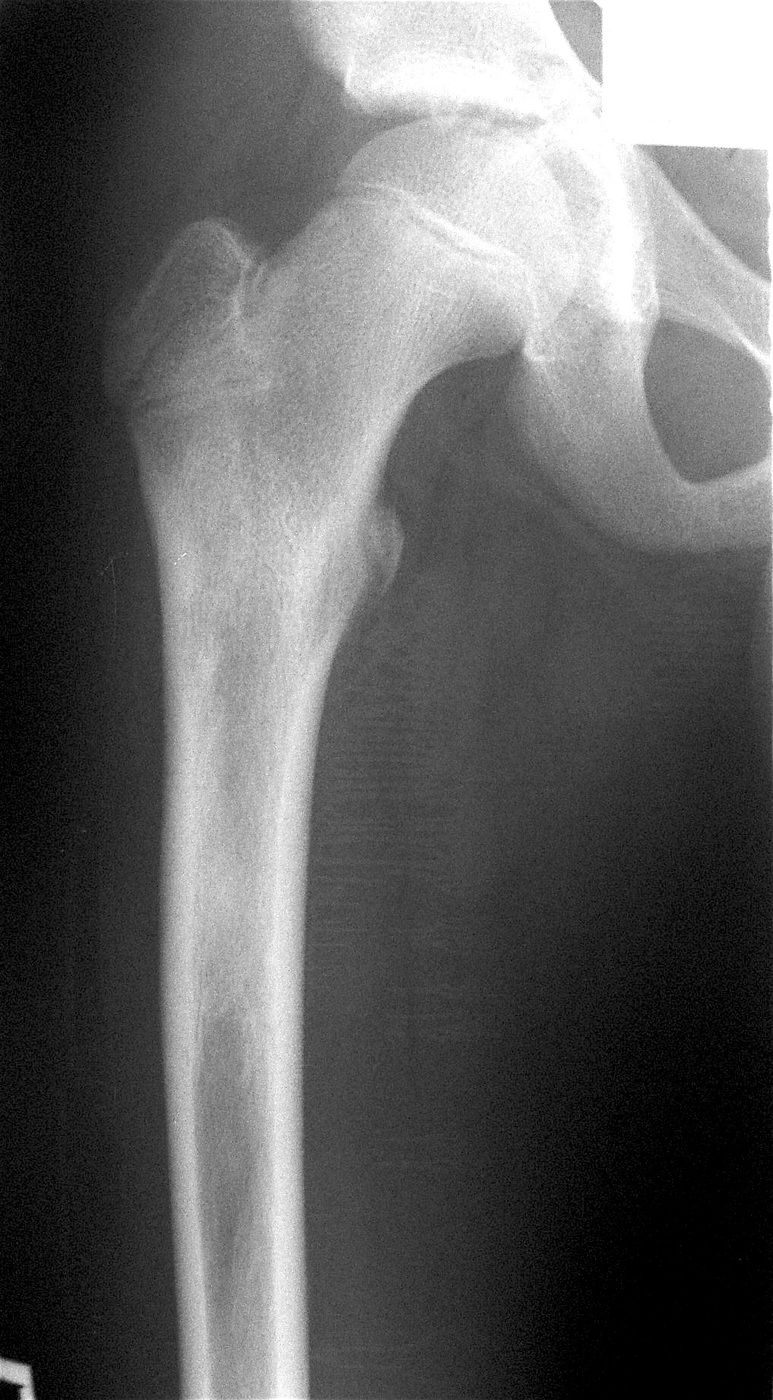

Остеоид-остеома проксимального метафиза правой бедренной кости.

Выполнена: внутрикостная резекция патологического очага, аллопластика материалом «Лиопласт».